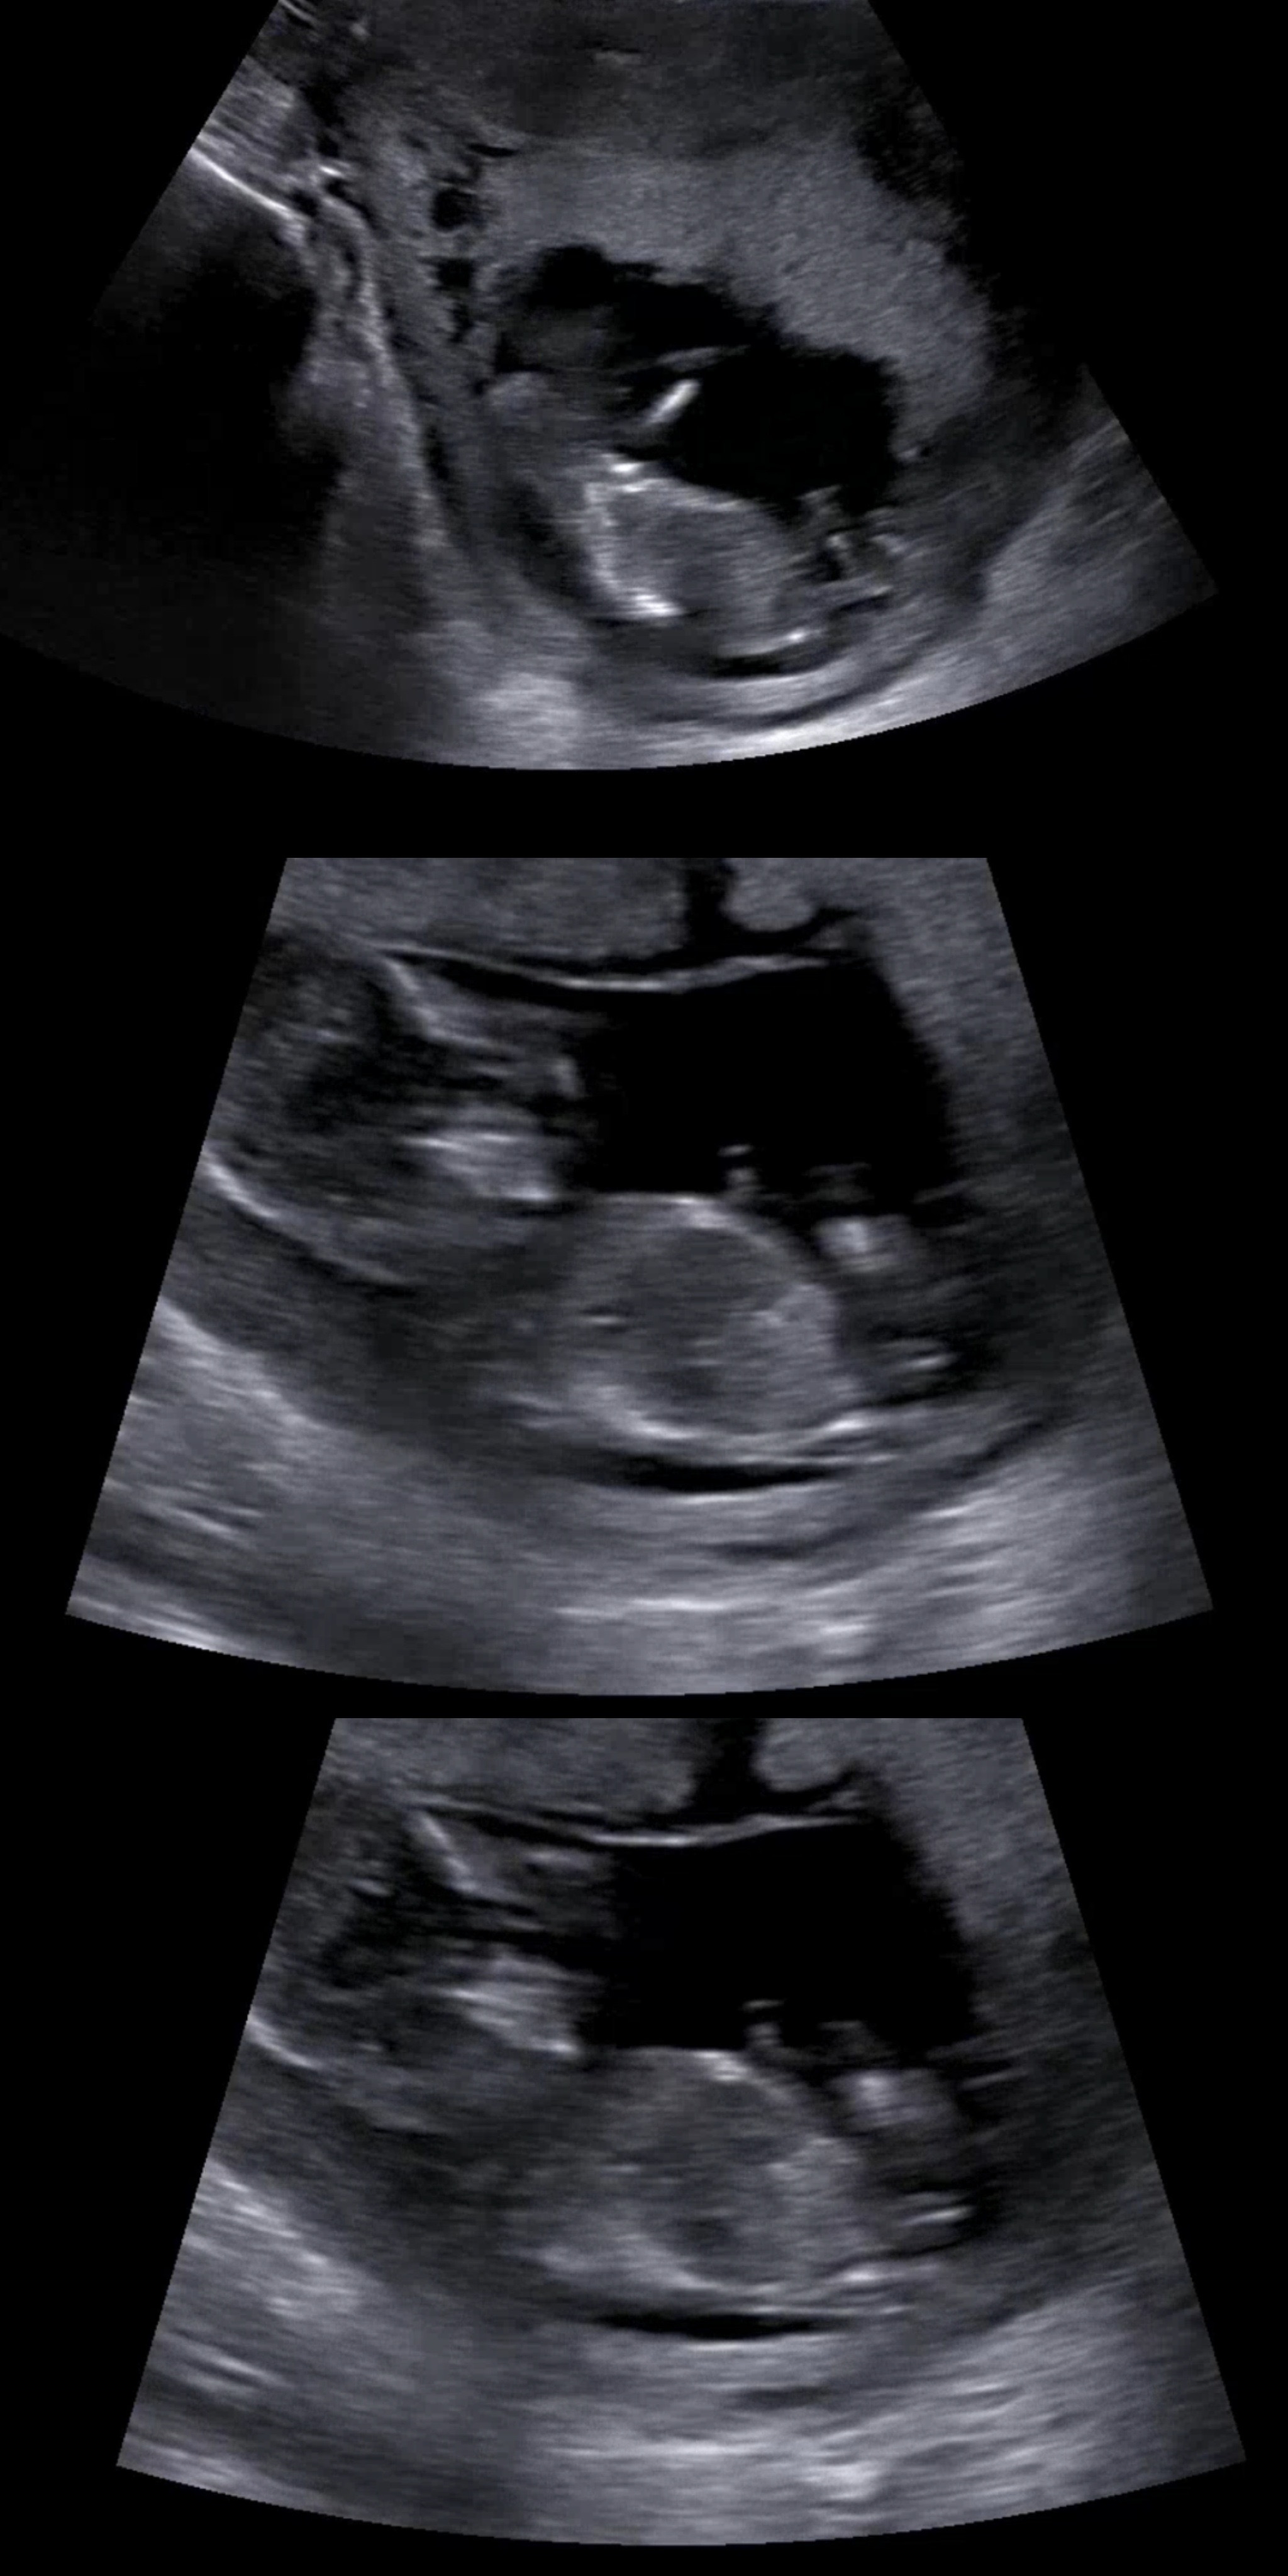

첫째가 아들이라 더 궁금하네요ㅋㅋ 첫재때는 12주 검사때 똭! 보였는데 둘째는 화질이 안좋아서 안보이더라구요ㅜㅜ 투표 마구마구 해주세용!! 12주 5일입니당